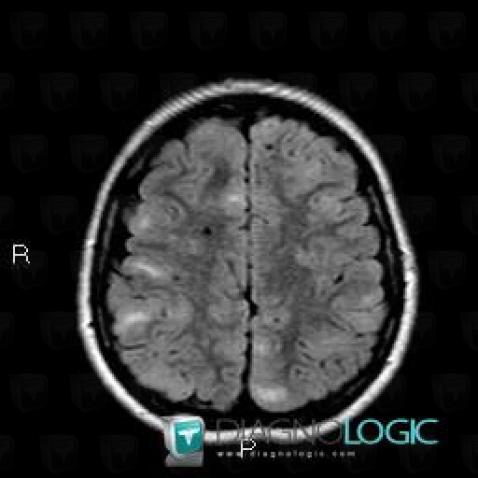

Here is the specific information in the key image above:

- Diagnosis Tuberous sclerosis (link to Hamartoma), Location(s) Cerebral hemispheres, with gamuts Multifocal intracranial lesions, Intracerebral T2W or FLAIR hyperintense lesion

- Diagnosis Hamartoma, Location(s) Cortico subcortical region, with gamuts Subcortical lesion, Cortical lesion

Here is the specific information in the key image above:

- Diagnosis Tuberous sclerosis (link to Hamartoma), Location(s) Ventricles / Periventricular region, with gamuts Periventricular anomaly seen in MRI, Ventricular wall nodules

Here is the specific information in the key image above:

- Diagnosis Tuberous sclerosis, Location(s) Cerebral hemispheres, with gamuts Parietal posterior or occipital T2WI or FLAIR hyperintense lesion

- Diagnosis Tuberous sclerosis (link to Hamartoma), Location(s) Cortico subcortical region, with gamuts Cortical lesion, Subcortical lesion